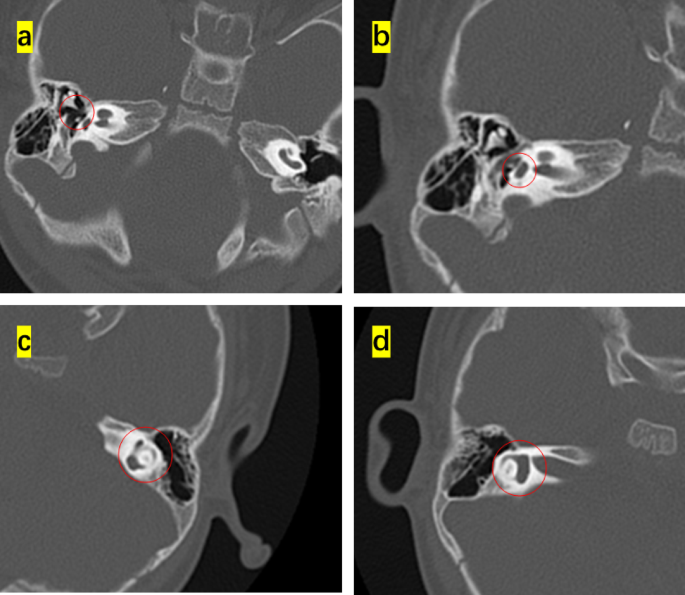

This study enrolled 16 children (8 months to 4 years old) that were diagnosed with diverse phenotypes of syndromic hearing loss and underwent CI. These included six, three, one, and six cases of WS, NS, KS, and CS, respectively. Children with different types of NCP-based hearing loss exhibit unique facial features: the iris of children with WS were heterochromic, and there were no abnormalities in the head and facial structure; the patients with NS had protruding foreheads, widened eye distances, and downward inclination of the eye fissures; the patient with KS had cracks on the long eyelid, with a slight outward rotation of one-third of the lower eyelid and a cup-shaped ear on the right side; all the CS patient were with predominant craniofacial anomalies involving the ears and eyes. Table 1 shows the main clinical features of the 16 children, specifically highlighting the ear malformations and the degree of developmental delay. There were observable differences between the types of syndromic hearing loss. WS and NS showed mild malformations of the middle and inner ear (Figs. 1 and 2). KS (Fig. 3) primarily exhibited malformations of the outer and middle ear structures. CS (Fig. 4) showed significant malformations in the outer, middle, and inner ear and showed varying degrees of stenosis or occlusion of the cochlea in different cases (Fig. 5). Cochlear nerve canal stenosis was observed in almost every CS case. Apart from WS, the other three syndromes showed clear craniofacial malformations, growth delay, and varying degrees of neurodevelopmental delay. Gesell scores were below the normal value of 85. Among the syndromes, WS and NS exhibited mild symptoms, KS showed more pronounced symptoms, and CS cases were the most severe.